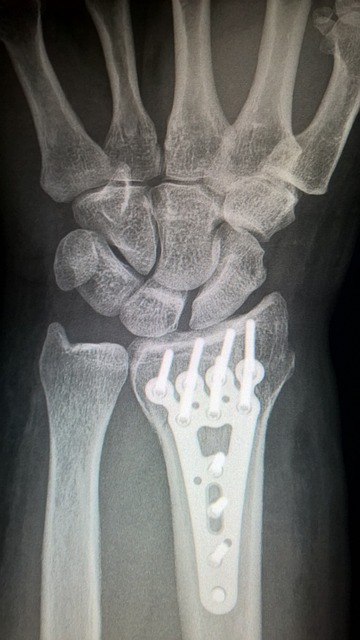

Broken bone fractures and broken bones are another common injury in traffic crashes and pedestrian accidents. When a pedestrian is hit by a vehicle, their body can be thrown in any number of directions, causing bones in lower and upper extremities, to fracture or break. Common, broken bones, that can be affected in a pedestrian accident include the arms, legs, ribs, and spine.

Symptoms of a broken bone can include pain, swelling, and difficulty moving the affected limb. Treatment for a broken bone can range from immobilization with a cast or brace to surgery, depending on the severity of the injury.